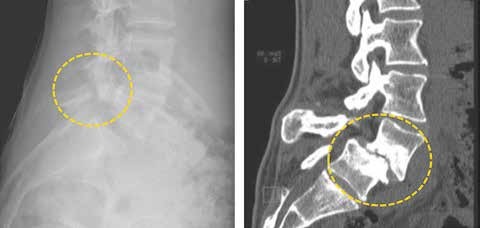

Die Behandlung von Spondylolyse und Spondylolisthese mittels Orthesen ist aus den Behandlungsempfehlungen weitgehend verschwunden 13 (Abb. 4). Dies ist nur damit erklärbar, dass Orthesen so dargestellt werden, als seien sie zur Ruhigstellung des gesamten Patienten vorgesehen. Das Gegenteil ist jedoch der Fall: Durch eine lokale Stabilisierung und Wirbelsäulenkorrektur wird eine beschwerdearme Aktivierung der Patienten erst wieder möglich.